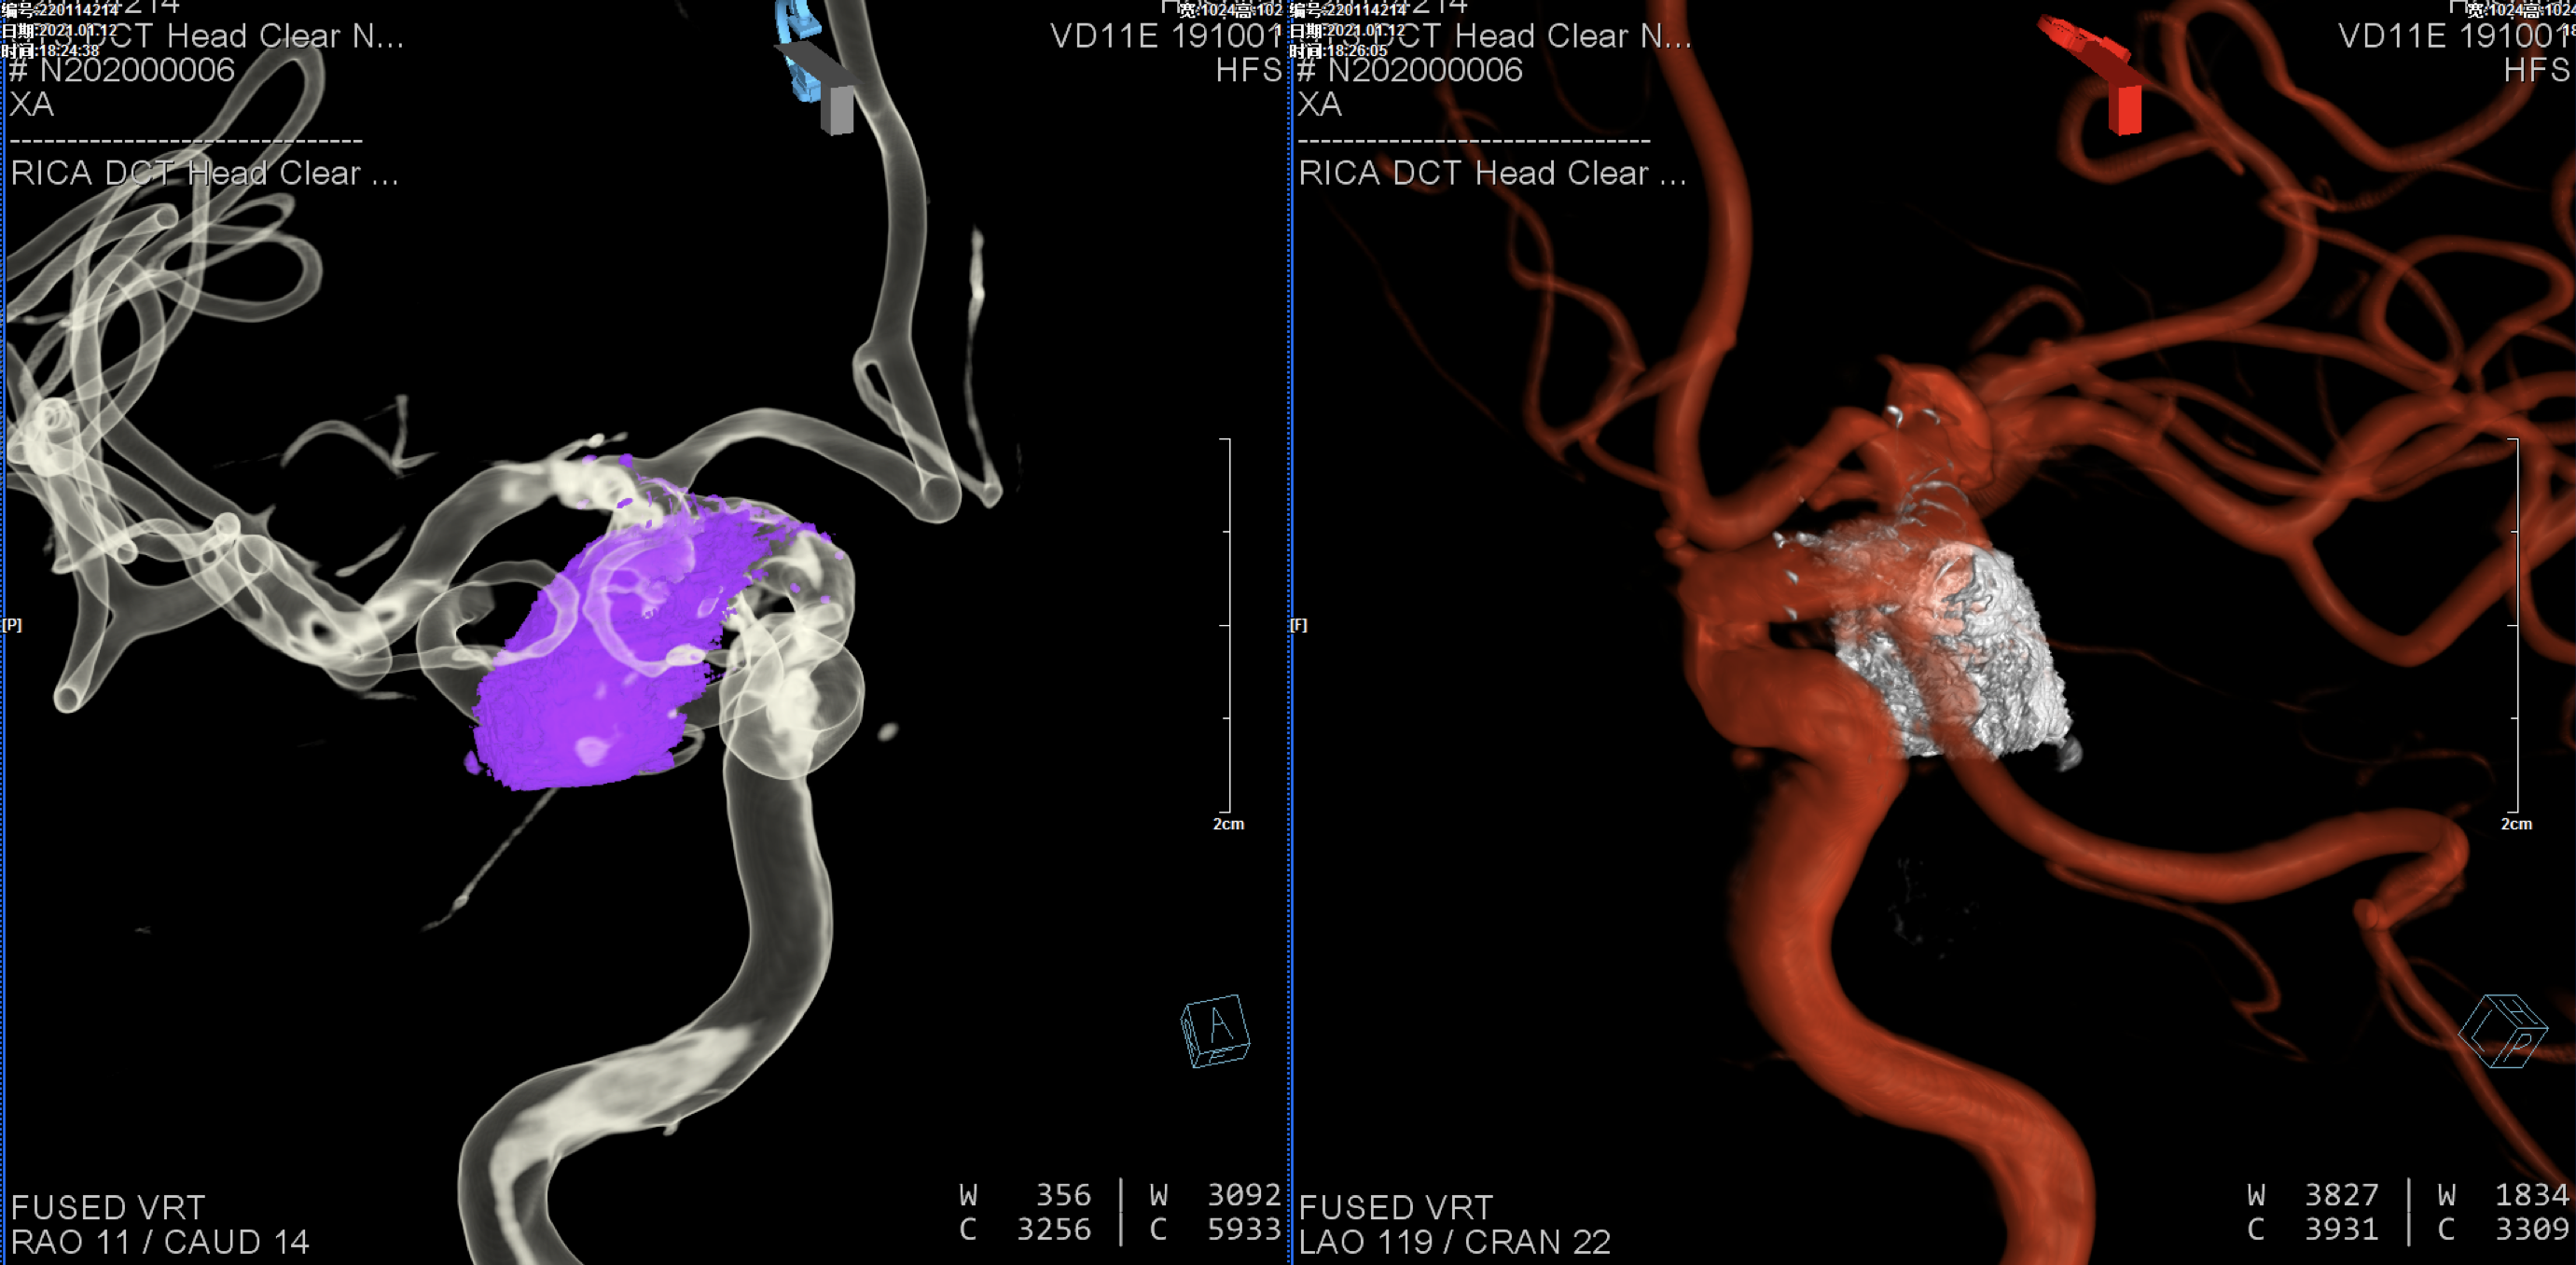

入院后完善头颅CTA:右侧颈内动脉后交通动脉瘤。

后交通动脉瘤大小约22mm*12mm。

右颈内动脉三维重建:粗大的后交通动脉自近心端瘤颈发出!闭塞后交通动脉可能会出现临床症状,似乎可以通过支架的推“灯笼”保护,但瘤体较大,尽可能栓塞完全,故考虑瘤腔内双微导管分区填塞!

术后三维重建:动脉瘤栓塞满意,后交通动脉保留!